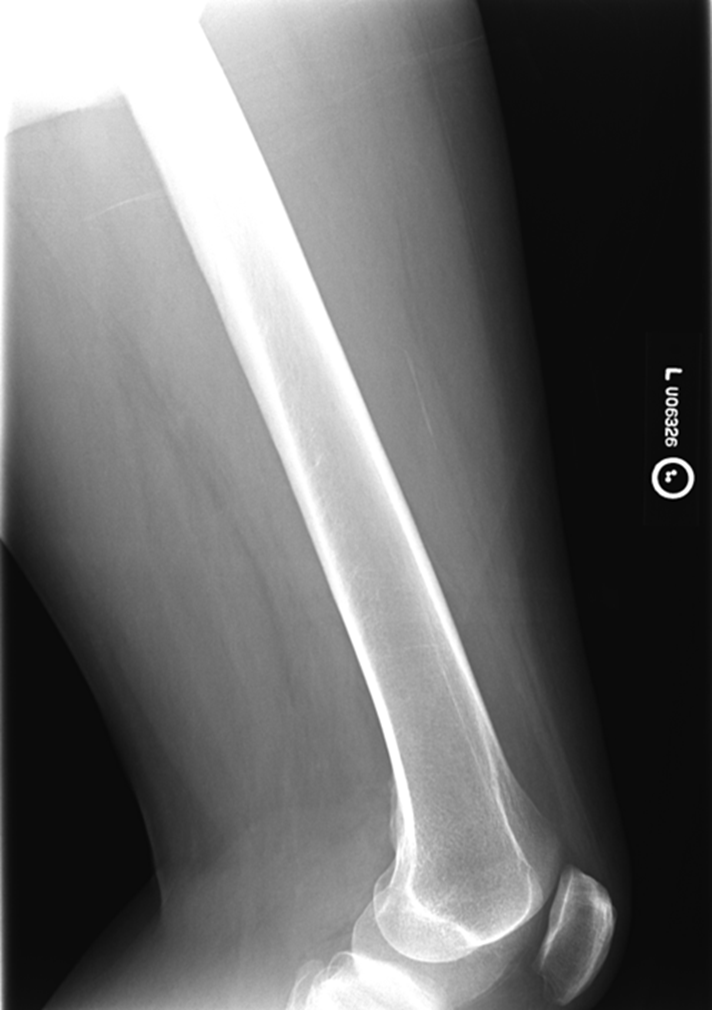

AP Femur

•Evidence of proper collimation and the presence of a side marker placed clear of the anatomy of interest

•Most of the femur and the joint nearest to the pathologic condition or site of injury (a second projection of the other joint is recommended)

•Femoral neck not foreshortened on the proximal femur

•Lesser trochanter not seen beyond the medial border of the femur or only a very small portion seen on the proximal femur

•No knee rotation on the distal femur

•Gonad shielding when indicated, but without the shield not covering proximal femur

•Any orthopedic appliance in its entirety

•Bony trabecular detail and surrounding soft tissues

Lesser trochanter is on, leg is not rotated in, under-rotated, hanging out too laterally

Leg was not internally rotated

No repeat, lesser trochanter can hardly see

Missing anatomy

slight medial rotation